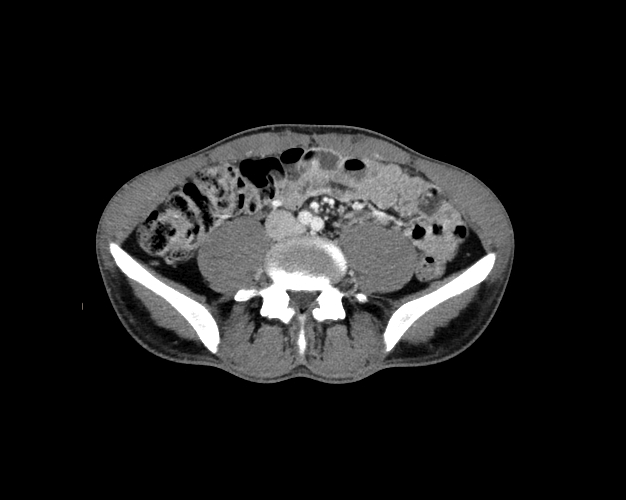

Body

Covers abdominal CT anatomy.